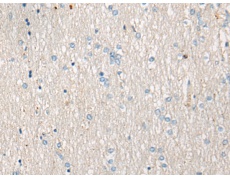

IHC positive control: |

Human brain |